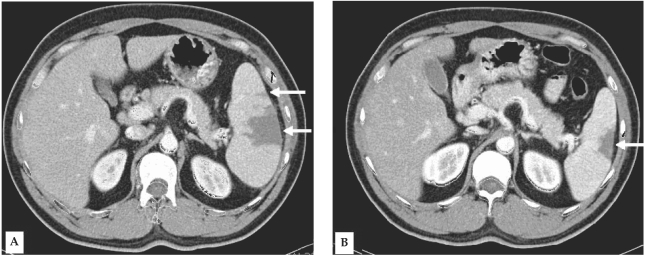

A 34-year-old man visited the Inha University Hospital in Incheon, Korea, complaining of a fever that had persisted for 5 days. Four days prior to the patient's visit, he had undergone ultrasonography at a nearby clinic, and was shown to be suffering from splenomegaly; the patient's spleen was approximately 14 cm long along the greatest axis. As malaria was not yet suspected in this case, medication was prescribed solely for symptomatic relief. At our outpatient department (OPD), fever and palpable splenomegaly were detected, and trophozoites and schizonts of P. vivax were detected at a density of 1.875 × 109/L. A blood examination revealed the following: hemoglobin level, 9.8 mM/L; white blood cell count, 3.8 × 109/L; and platelet count, 47 × 109/L. Serum aspartate aminotransferase, alanine aminotransferase, and bilirubin levels were as follows: 1.77 mM/L, 2.42 mM/L, and 28.9 µM/L, respectively. The patient was prescribed a course of chloroquine (25 mg/kg over 48 hr) and was instructed to take primaquine after the fever had subsided. Six days later, the patient made another visit to the OPD, due to pain in the left upper abdomen, accompanied by pain in the left shoulder. The patient was afebrile, but continued to exhibit palpable splenomegaly. Upon admission, computed tomography (CT) of the abdomen revealed findings consistent with splenic infarction, i.e., multiple areas of low attenuated density in the enlarged spleen (Fig. 1A). Over the 3 days of hospitalization, the patient's other vital signs remained stable. No malarial trophozoites were observed on the blood smear. The patient's hemoglobin level, white blood cell count, and platelet count were 8.0 mM/L, 10 × 109/L, and 336 × 109/L, respectively. Liver function tests and tests for markers of hypercoagulable conditions, such as protein C or antithrombin III, were all normal. Upon discharge, the patient was prescribed a 14-day regimen of primaquine (15 mg/day), coupled with an analgesic that promptly relieved the patient's abdominal pain. 10 weeks later, the patient evidenced no symptoms consistent with splenic infarction, and a follow-up abdominal CT revealed partial resolution of the splenic infarction (Fig. 1B).

In cases in which splenic infarction is suspected, it can be readily diagnosed by a CT showing multiple wedge-shaped regions of low attenuation, which are distinctively different from those observed on CT images of splenic rupture or subcapsular hematoma (Miller et al, 2004). Ultrasonography is another tool that can be used in the evaluation of splenomegaly, but this technique is less sensitive than CT during the acute stage of infarction. Thus, it remains uncertain as to whether asymptomatic splenic infarction was actually present in our patient on day two. Splenic angiography, if performed, will show wedge-shaped regions of reduced perfusion corresponding to the infarction patterns observed on CT. Splenic abscess can be excluded by radiologic findings and clinical features, as an abscess is normally accompanied by systemic symptoms (Green, 2001). Although the symptoms of perisplenitis are purported to be more severe than those associated with 'usual' splenomegaly (Read et al, 1946), it remains uncertain as to whether this illness is truly different from 'usually symptomatic' splenomegaly.